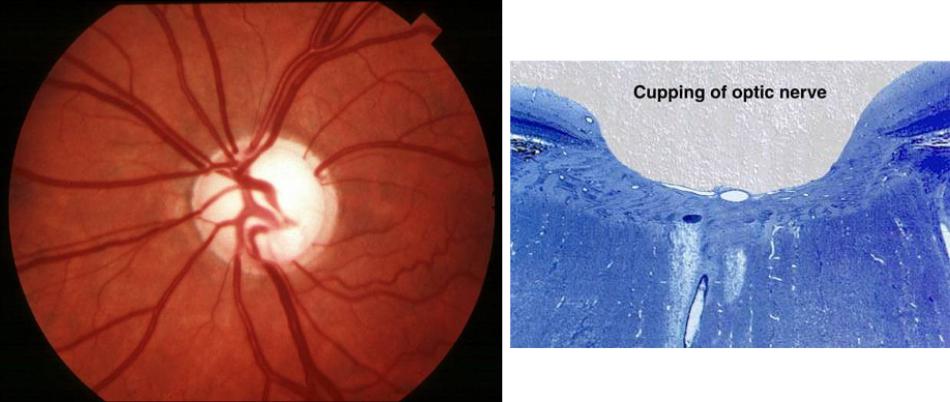

Атрофия зрительного нерва Лебера: Симптомы и лечение